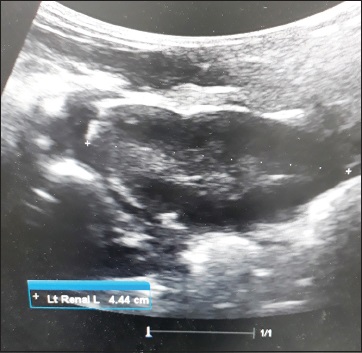

Normal ultrasound dimensions of newborn kidneys in Southwest Nigeria

Adejumoke I Ayede, Atinuke M Agunloye, Richard B Olatunji, Ibilola O Fawole, Ayodele S Jegede, Samuel I Omokhodion (Author)

128-134